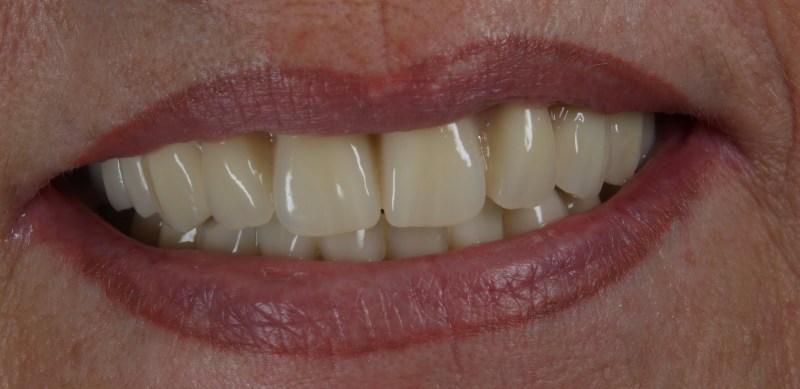

Vom Langzeitprovisorium zur TEK 1 Arbeit